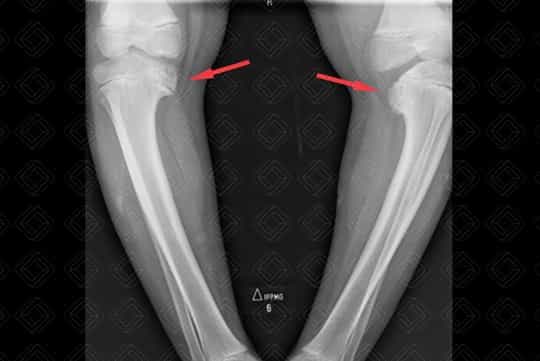

Texto alternativo para a imagem Figura 1. Crédito: Dra. Elazir Mota - Rio de Janeiro/RJ

Descrição da imagem: Radiografia dos joelhos em AP e perfil. Geno varo bilateral e importante arqueamento dos fêmures. Tíbias varas observando-se alteração morfoestrutural das metáfises e epífises mediais (setas vermelhas).

• Radiografia dos joelhos: Na maioria dos casos é realizado com radiografias dos joelhos em AP. A radiografia vai demonstrar o geno varo e anormalidades na tíbia proximal, que consistem na fragmentação e irregularidade da porção posteromedial das metáfises e deficiência da porção medial das epífises. As fises podem permanecer abertas na sua porção medial devido ao crescimento prejudicado;